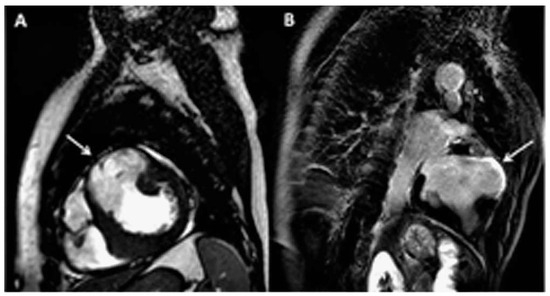

Structural cardiovascular disease is responsible for a significant disease load worldwide. Although currently used replacement procedures are efficacious and change the deadly evolution of many structural cardiovascular defects, the clinically used r...